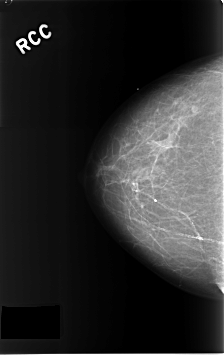

C_0303_1.RIGHT_CC

RIGHT_CC LINES 4608 PIXELS_PER_LINE 2904 BITS_PER_PIXEL 12 RESOLUTION 50 NON_OVERLAY